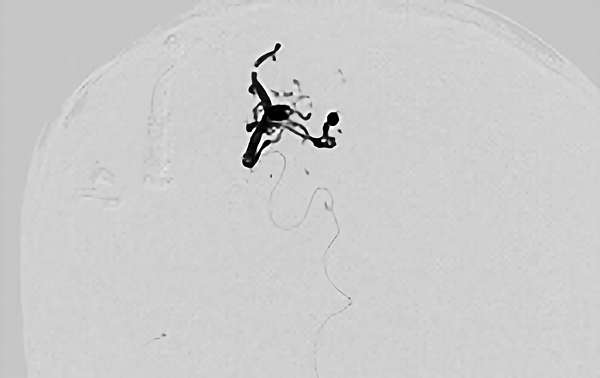

'26年3月

出血性脳動静脈奇形

10代

院内外来

No.1620 手術前

No.1620 手術中

No.1620 手術後